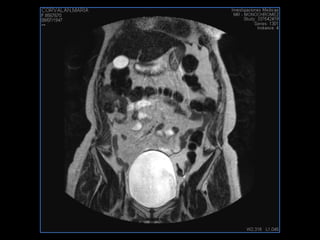

LIC ALEJANDRA GALVEZ RM DE ABDOMEN

PROTOCOLO pelvis SAG T2, Y FAT SAT (FINOS) AXIAL T1  AX FAT SAT CON   GADOLINIO :  AX T1 Y COR T1 SAT: NO  FASE: RL THK: 3MM  COIL:  GAP: (FACTOR 1.4) 1MM FOV: 40 CM NEX:2 SINCRONIZACION RESPIRATORIA EN 3 O 4 CICLOS ALE

resonancia de abdomen